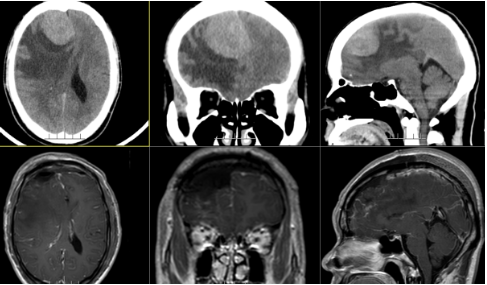

阿明今年48岁,像往常一样刚刚工作完回家吃饭,突然间头痛剧烈并出现干呕。以为是感冒受寒突然引起的,未引起重视,但是家人还是不不放心,立即带去当地医院。检查头颅CT示右侧额部占位性病变,瘤周水肿严重,当地医生建议上级医院继续治疗。

张良主任看过CT说这是右侧额部大脑镰旁示一团块状占位性病变,以邻近颅骨及大脑镰呈宽基底,呈囊实性,实性部分呈稍高密度影,囊性部分呈低密度影,病变边界清,大小约49×52×56mm。

安排住院需要择期手术,入院后完善相关术前检查,于2023-01-18在手术室全麻下为患者行“右侧额部脑膜瘤切除术”。

术后病理提示:初步报告:(右侧额部)形态学初步考虑为非典型脑膜瘤,CNS WHO2级。术后MRI提示:右侧额部占位性病变切除术后改变。